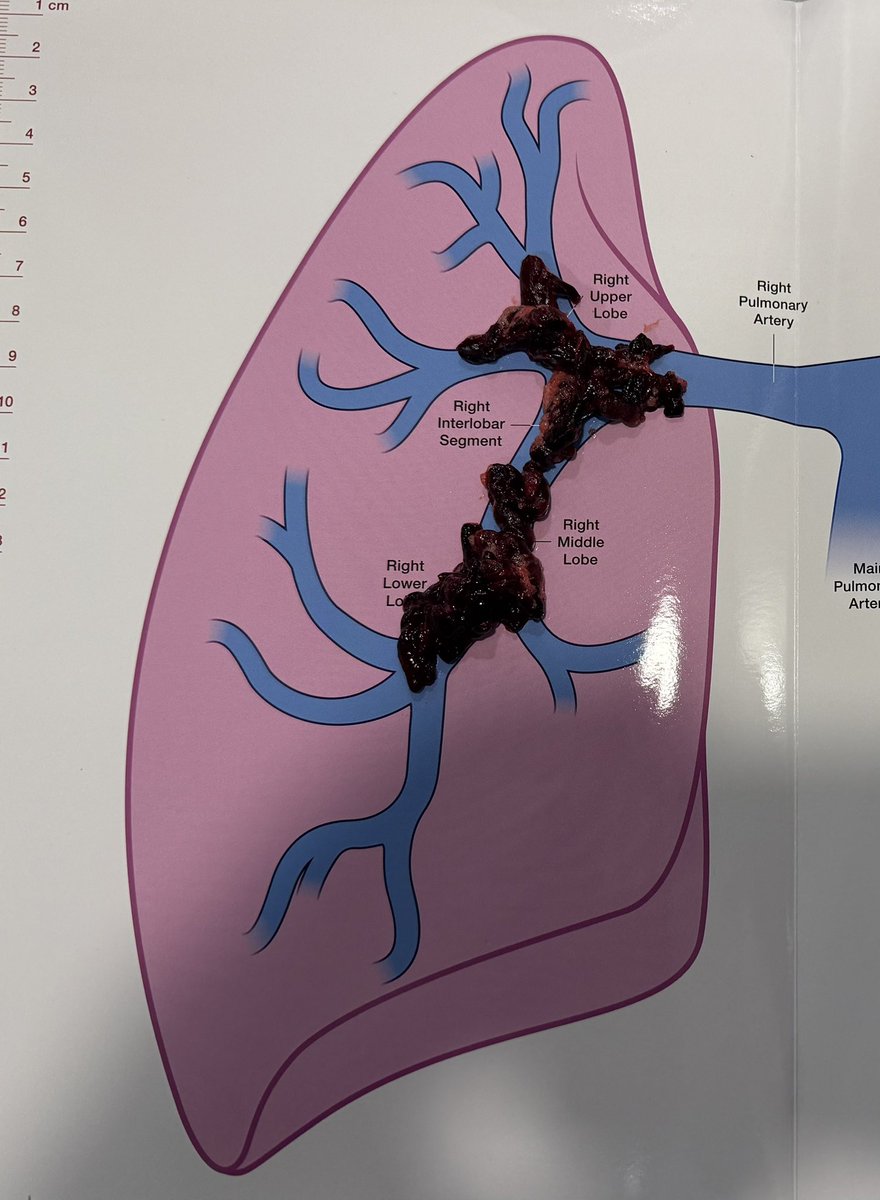

Large volume IVC thrombectomy and mod sed TIPS done same session - patient was able to be discharged and make it to her sons wedding - she fit much better into her dress with no ascites!